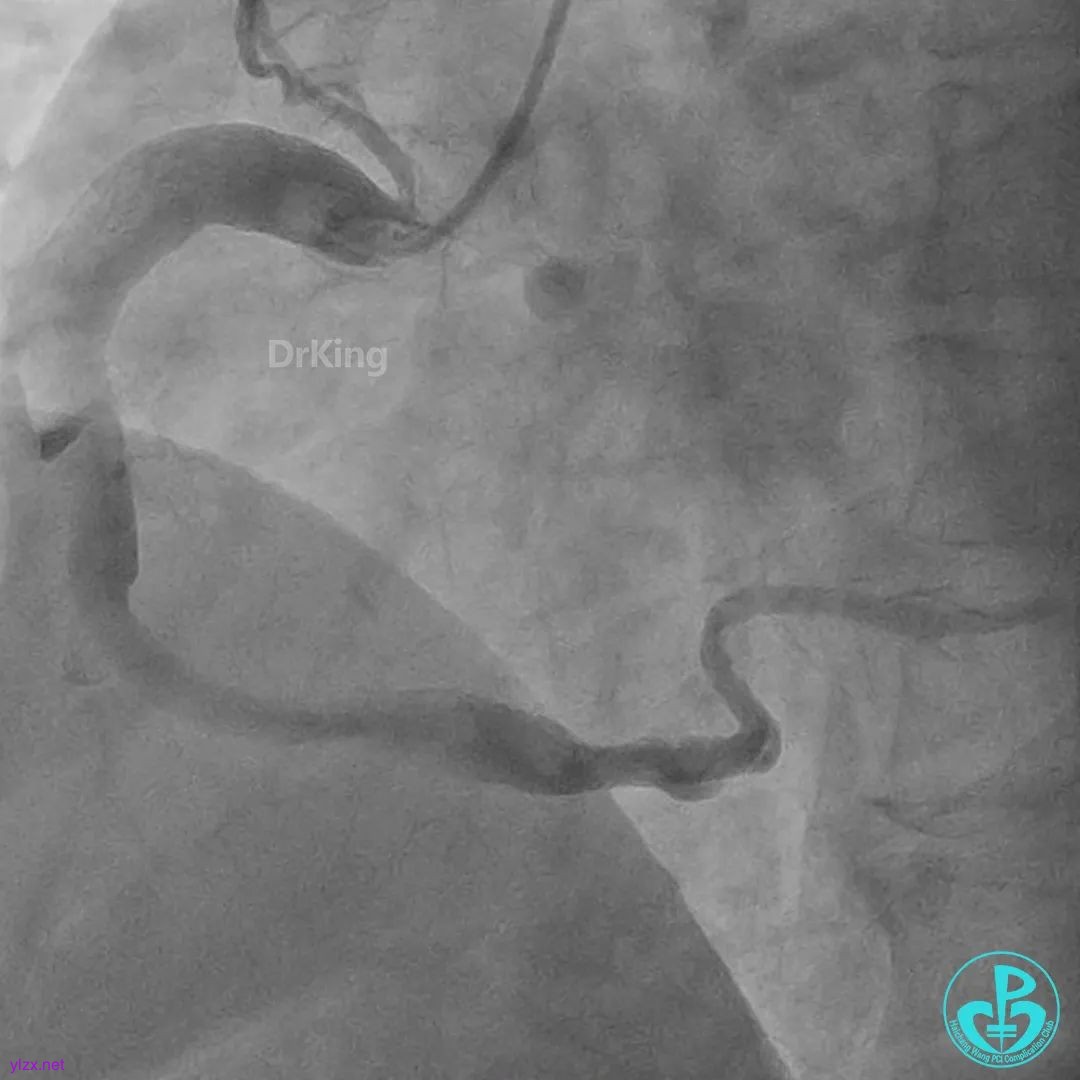

右冠脉粗大,近中段瘤样扩张明显,中段闭塞,局部可见大块血栓影。

首选开通右冠脉,导丝到达闭塞段远端,球囊扩张后,可见大量血栓,抽吸导管反复抽吸出大量血栓。冠脉内推注尿激酶原20mg,复查造影提示右冠脉远端显影,调整导丝至远段。

球囊再次扩张闭塞段,并对后降支及左室后支开口行对吻球囊扩张,复查造影示血流3级,无夹层行成,右冠脉远段仍可见血栓影。